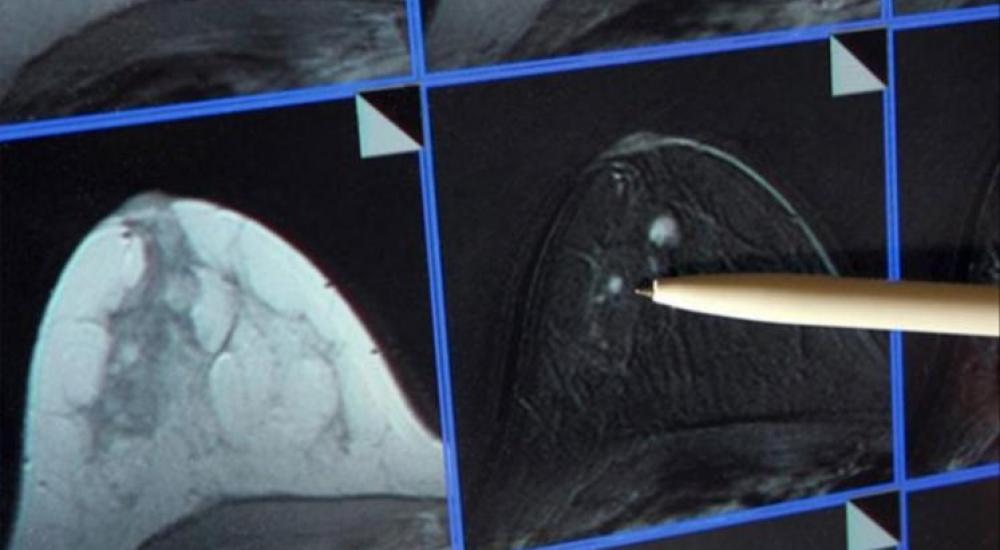

أفادت دراسة جديدة بأن نصف مرضى سرطان الثدي يمكن أن يستفيدوا من إضافة هرمون البروجسترون الأنثوي إلى علاجهم. فقد اكتشف العلماء أن هذا الهرمون يمكن أن يوقف نمو الورم.

وتظهر الدراسة الجديدة التي نشرتها صحيفة ديلي تلغراف البريطانية كيفية تخاطب مستقبلات هرمون البروجسترون مع المستقبلات الأخرى الحساسة للبروجسترون، التي تزيد سرطان الثدي في عدد كبير من الحالات، وهذا الأمر له تأثير استخدام المكابح على قدرة مستقبلات البروجسترون لتحفيز الأورام.

يشار إلى أن نحو 50 ألف حالة جديدة لسرطان الثدي تشخص في بريطانيا كل عام، ويعتقد الباحثون أن نحو النصف يمكن أن يستفيدوا من هذا الاكتشاف.

وهذا يعني إمكانية وقف المرض من الانتشار في بقية أجزاء الجسم، وهو ما يزيد الآمال في علاج جديد للمرض منقذ للحياة.